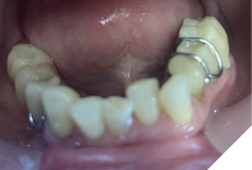

A 72-year-old Caucasian female presented with long-standing TMJ discomfort and missing teeth. She was diagnosed with partial mandibular edentulism (missing 37, 45, 46, 47), generalized attrition, and arthrogenic TMD due to posterior bite collapse. Her periodontal condition was stable.

After informed consent, Phase I began with delivery of a Gelb appliance (Fig. 3ABC), which was adjusted periodically until achieving the treatment VDO. Phase II involved stabilization at this VDO. Teeth 36, 35, 43, and 44 were prepared simultaneously, and impressions (Henry Schein VP MIX) and bite registration (Kopy ultra-fast VPS) were taken using the palatal jig.